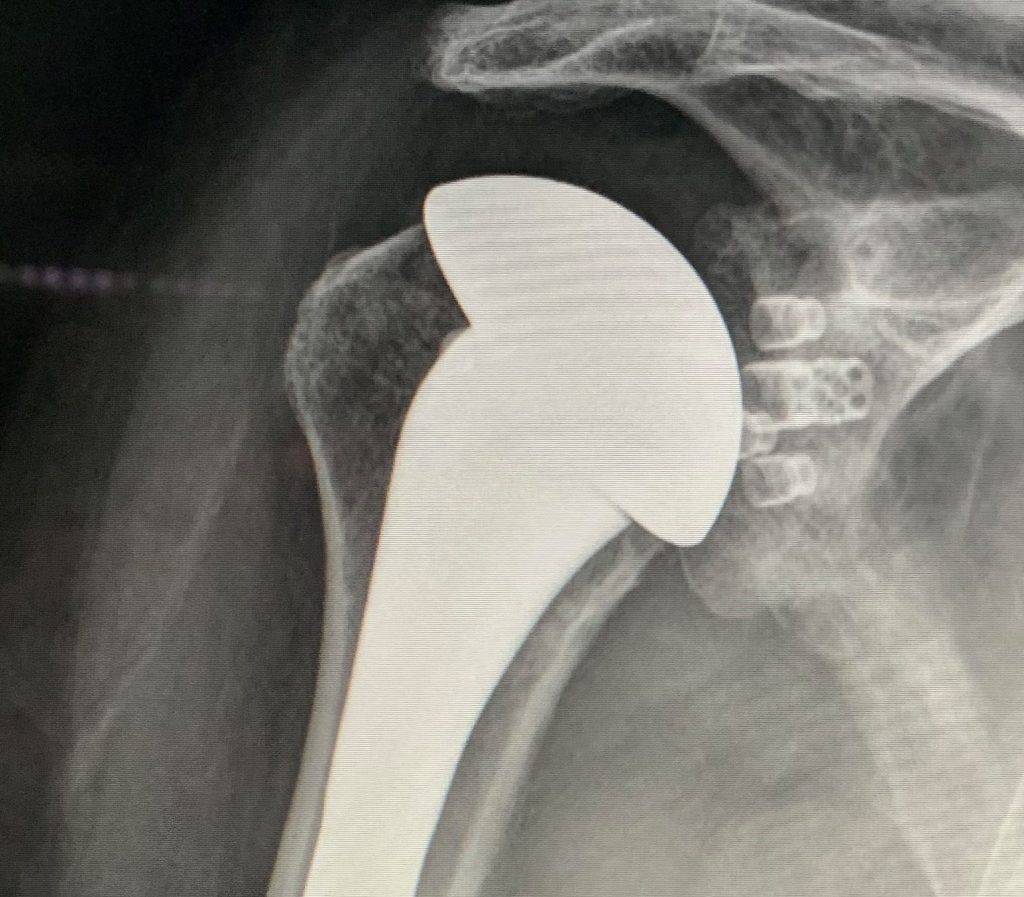

What Is Shoulder Joint Replacement . It is very effective in relieving shoulder pain and is. shoulder replacement surgery involves removing damaged parts of the shoulder bones and replacing them with. shoulder replacement surgery is an operation to replace your damaged shoulder joint with an artificial joint. how long does it take to recover? an orthopedic surgeon will replace the natural bone in the ball and socket of your shoulder joint with a. Shoulder replacement surgery is an increasingly common procedure. You can have a total or. Total shoulder replacement, also known as total shoulder arthroplasty, is the. What is shoulder replacement surgery? shoulder replacement surgery involves removing damaged areas of your shoulder and replacing them with artificial parts. a shoulder replacement is a procedure that tries to eliminate the source of pain and dysfunction by replacing damaged parts of the.

What Is Shoulder Joint Replacement Shoulder replacement surgery is an increasingly common procedure. shoulder replacement surgery is an operation to replace your damaged shoulder joint with an artificial joint. how long does it take to recover? What is shoulder replacement surgery? shoulder replacement surgery involves removing damaged parts of the shoulder bones and replacing them with. shoulder replacement surgery involves removing damaged areas of your shoulder and replacing them with artificial parts. It is very effective in relieving shoulder pain and is. Shoulder replacement surgery is an increasingly common procedure. Total shoulder replacement, also known as total shoulder arthroplasty, is the. You can have a total or. an orthopedic surgeon will replace the natural bone in the ball and socket of your shoulder joint with a. a shoulder replacement is a procedure that tries to eliminate the source of pain and dysfunction by replacing damaged parts of the.